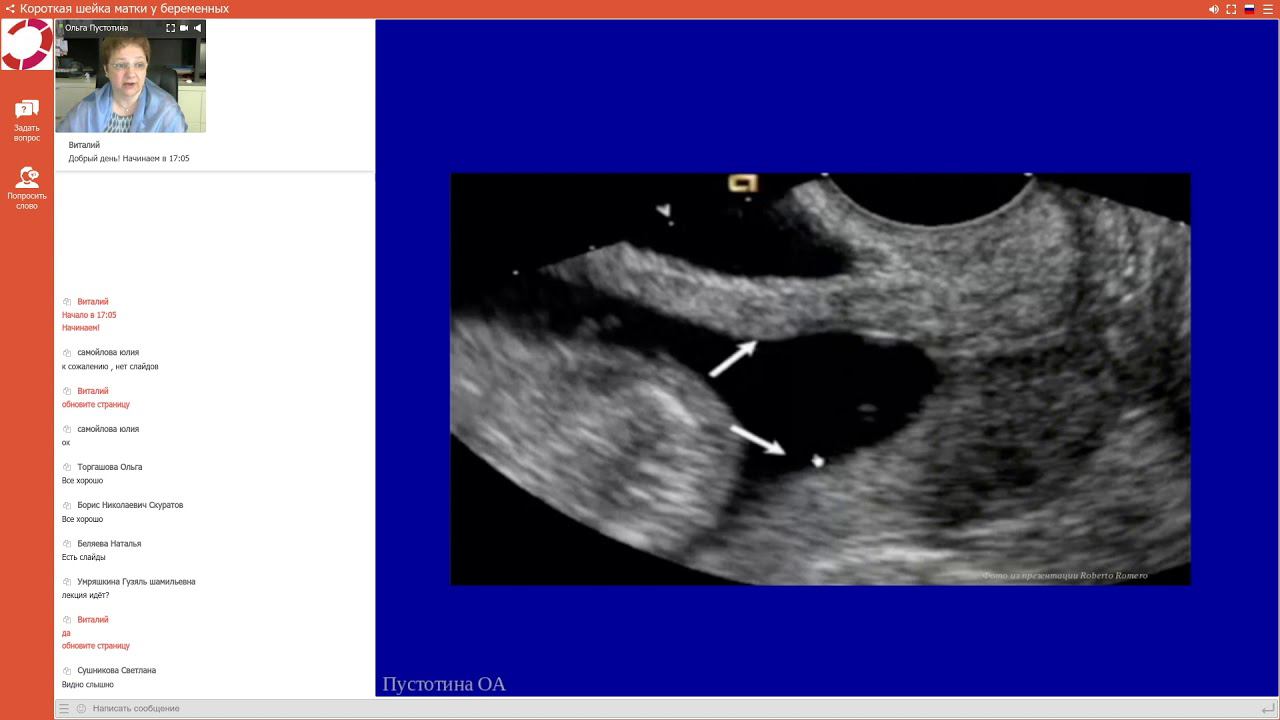

Экспертология | Короткая шейка матки у беременных Пустотина О.А.

Короткая шейка матки у беременных: определение, диагностика, тактика ведения Социальные сети ЭКСПЕРТОЛОГИИ Web: http://expertologiya.ru/ Авторские мастер-классы от руководителя проекта Пустотиной О. А. : http://expertologiya.ru/education Facebook: https://www.facebook.com/expertologiya Instagram: https://www.instagram.com/expertologiya/